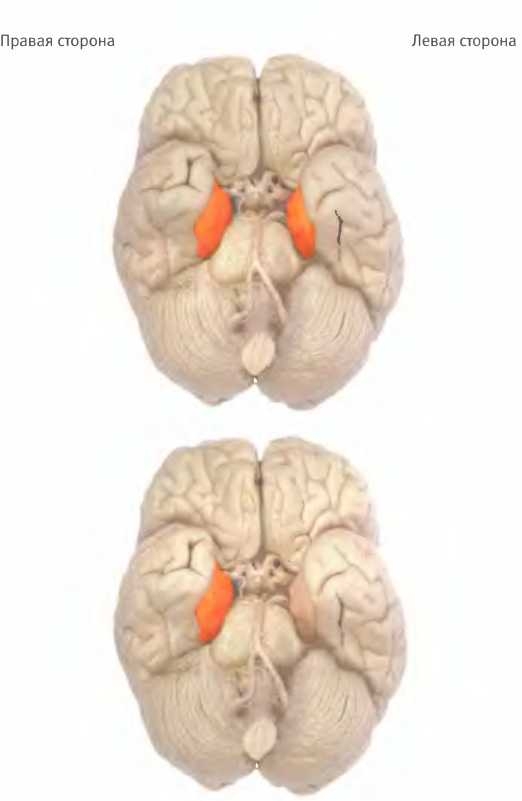

Гиппокамп обоих полушарий активируется, когда человека просят вспомнить какие-либо события, происходившие с ним самим, то есть обратиться к эпизодической памяти (вверху).

При ориентировании на знакомой местности гиппокамп тоже активируется, но только в правом полушарии (внизу).